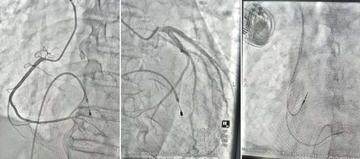

• 生命接力 守护心跳——西安市中心医院成功救治高陵区心脏骤停危重患者

近日,来自西安市高陵区的81岁马先生经历了一场惊心动魄的生命救援。从当地医院的紧急心肺复苏,到通过医联体绿色通道迅速转运,再到西安市中心医院成功完成起搏器植入术——这场跨越区域的医疗接力,成功挽救了老人的生命,彰显了医联体协作下高效、专业的救治能力。 突发险情,接力启动 老人在家中被家属发现时已意识不清,呼之不应,情况万分危急。家属立即拨打120,将其紧急送往高陵区医院。到达医院后